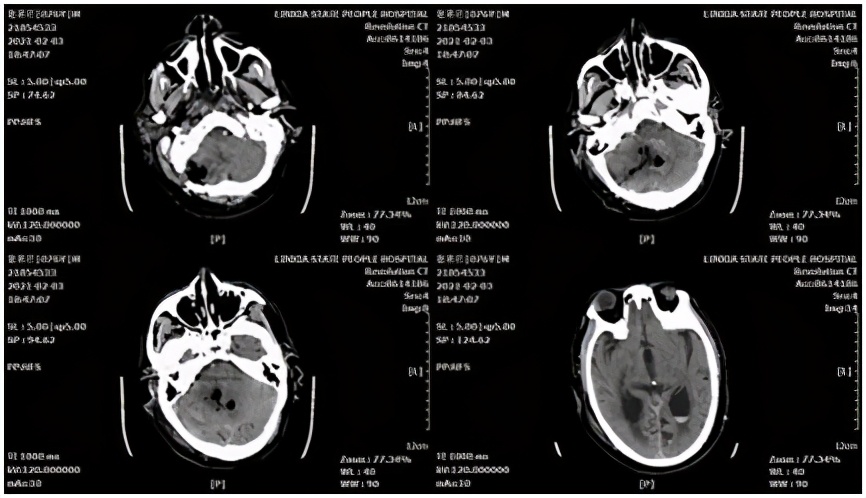

脑叶出血病例,患者女性,61岁。主因"“突发意识障碍、恶心、呕吐5小时”",于2021-02-20收入院。头颅CT示:左侧颞顶叶脑内血肿。

术前CT

术中采用微骨窗入路,保护缺血半暗带,最终 回复 良好。

术后CT